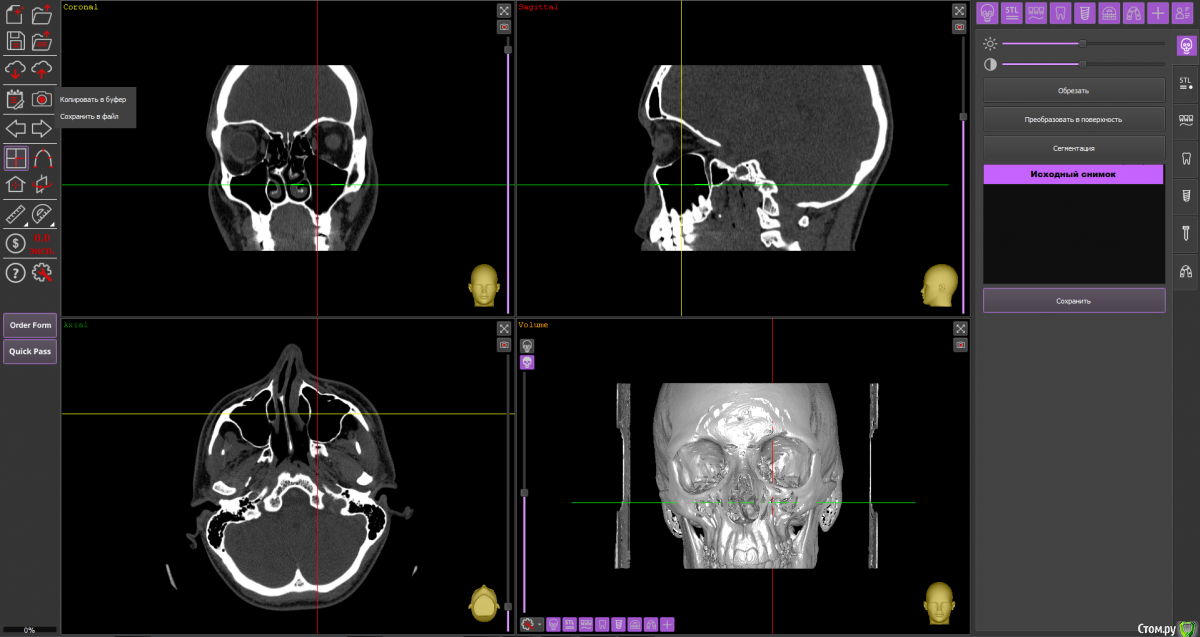

Dmitriytd Опубликовано 19 августа, 2020 Поделиться Опубликовано 19 августа, 2020 Здравствуйте, пожалуйста, посмотрите КТ( сделано в стоматологической клинике). Беспокоят проблемы с носом(постоянные прозрачные выделения, боли в пазухах, особенно при наклоне головы вниз). Знакомый лор посоветовал проверить на одонтогенный гайморит и я вспомнил, что делал КТ два года назад.Ссылка на КТ:https://yadi.sk/d/64pLNRildrWt5A Ссылка на комментарий

Dmitriytd Опубликовано 11 сентября, 2020 Автор Поделиться Опубликовано 11 сентября, 2020 Два года -кт не актуаленЗдравствуйте, сделал новое КТ. Пожалуйста, посмотрите:https://yadi.sk/d/1sbzO9z0QrurZg Ссылка на комментарий

wladdX Опубликовано 11 сентября, 2020 Поделиться Опубликовано 11 сентября, 2020 На мой взгляд, ничего примечательного в верхнечелюстных синусах нет. 1 Ссылка на комментарий